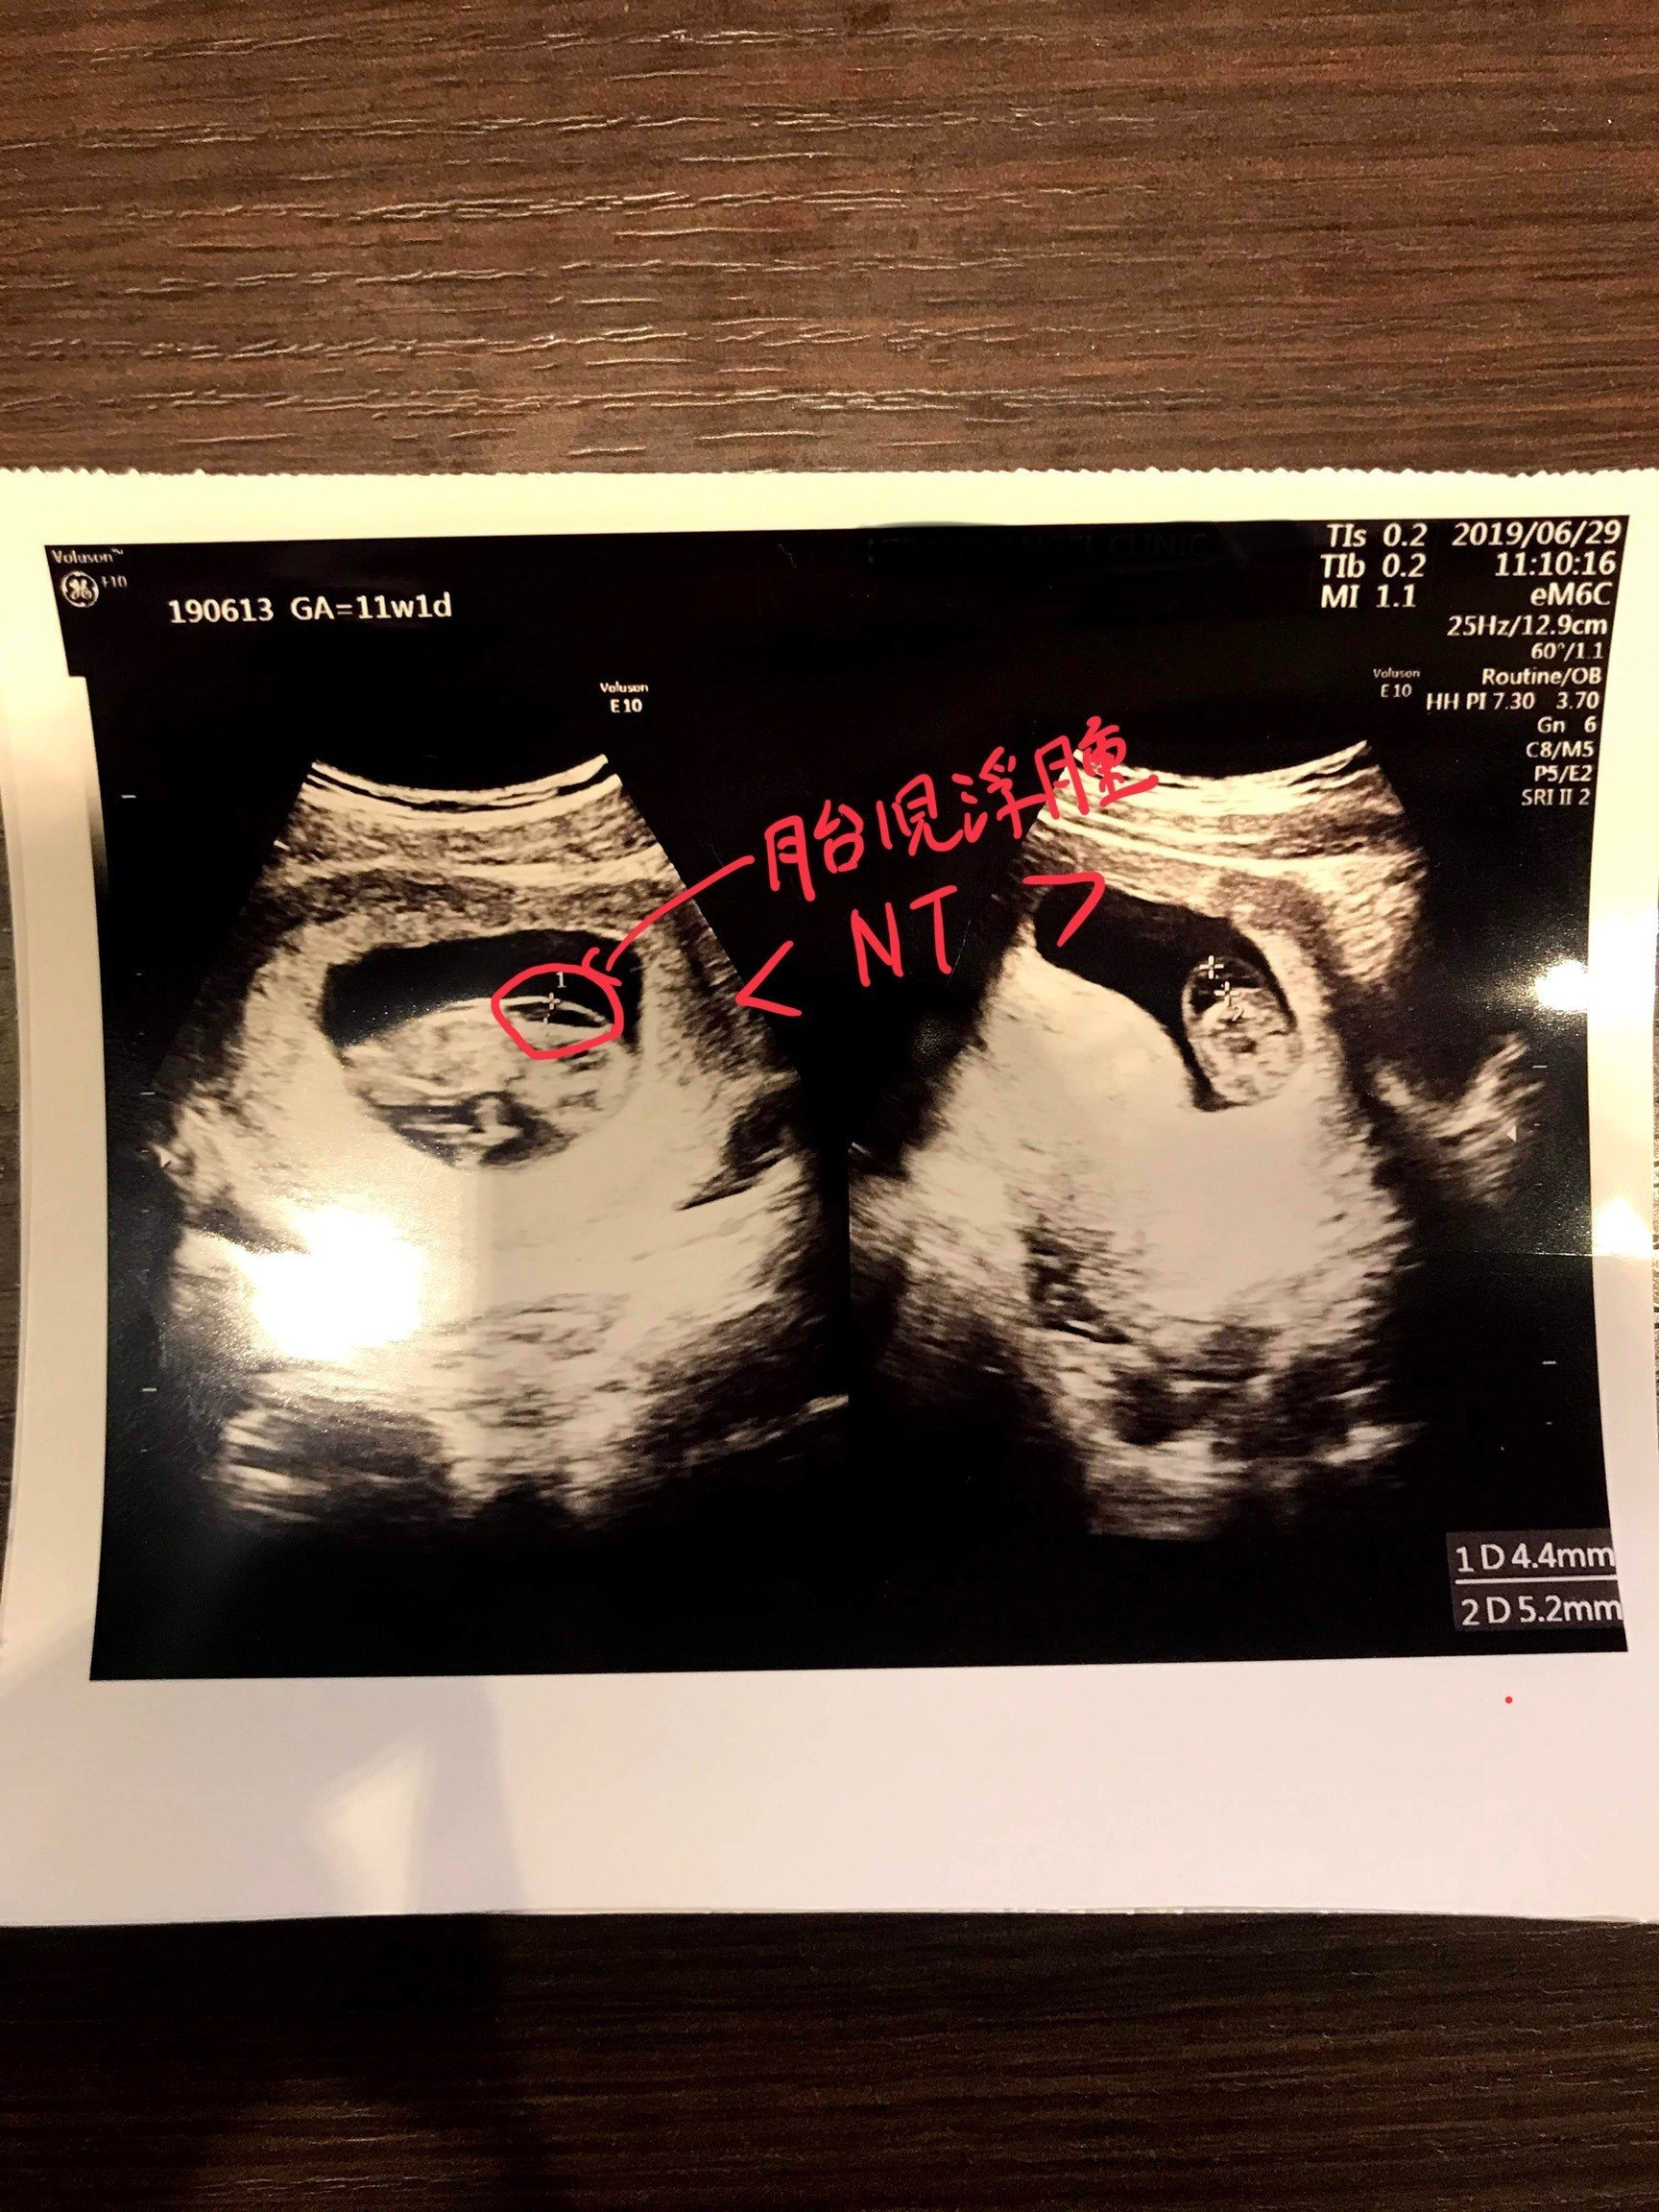

胎児ドック Nt計測 つれづれえび育成記

エコー画像 首のむくみ1 4 Nt 胎児頚部透過像 39歳で出産予定 10歳年上夫と不妊治療 By北国のマリー

胎児ドック スクリーニング検査 を受けた人が 内容や費用を詳しく説明するよ Techガールのuslife

妊娠12週前後 赤ちゃんの首の後ろの浮腫 Nt と胎児ドック しのくろ育児録

02 妊娠初期 胎児の頸部浮腫 Nt 妊娠11 13週でcheck 深谷産婦人科 医学情報

胎児超音波ーマーカー検査とは ヒロクリニック

胎児の首の後ろのむくみ 浮腫 Nt とは 妊娠初期 All About

Nt Nuchal Translucency について 出生前検査 Nipt 遺伝カウンセリング 妊婦健診 エコー検査 産科 婦人科 産婦人科

胎児の首の後ろのむくみ 浮腫 Nt とは 妊娠初期 All About

胎児の首のむくみ Nt クリフム夫律子マタニティクリニック